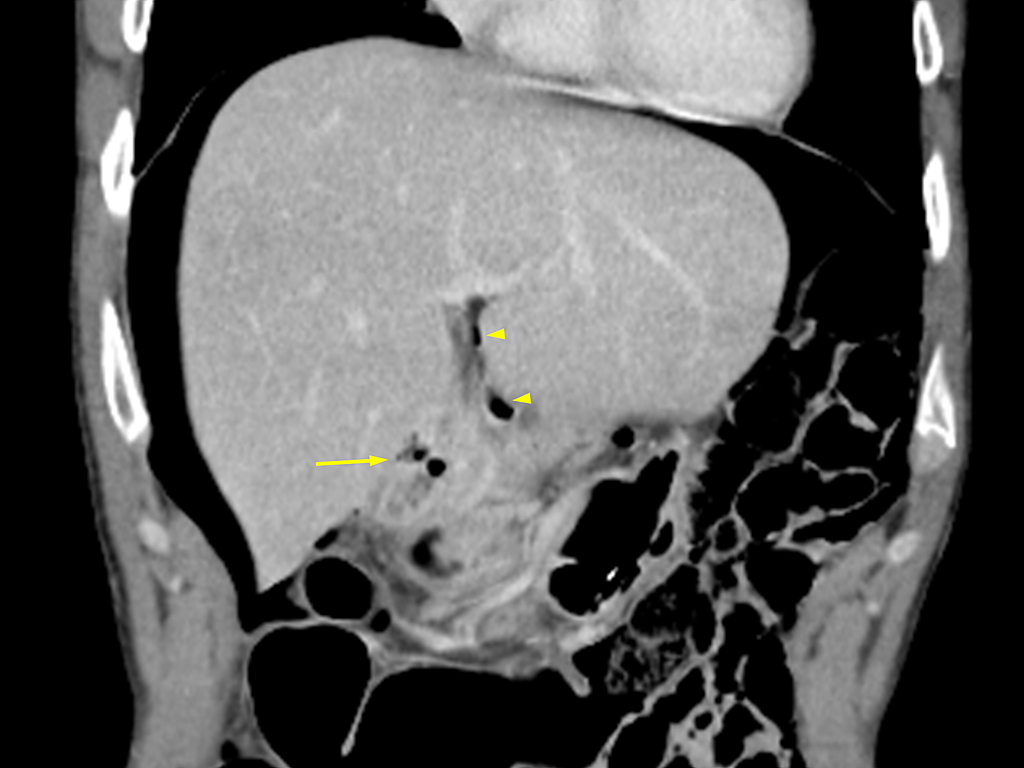

Image TDM en coupe axiale et

dans la paroi de estomac ( coupe TDM coronale ) |

Image radiologique TDM

peritoneale ( peritonite ) |